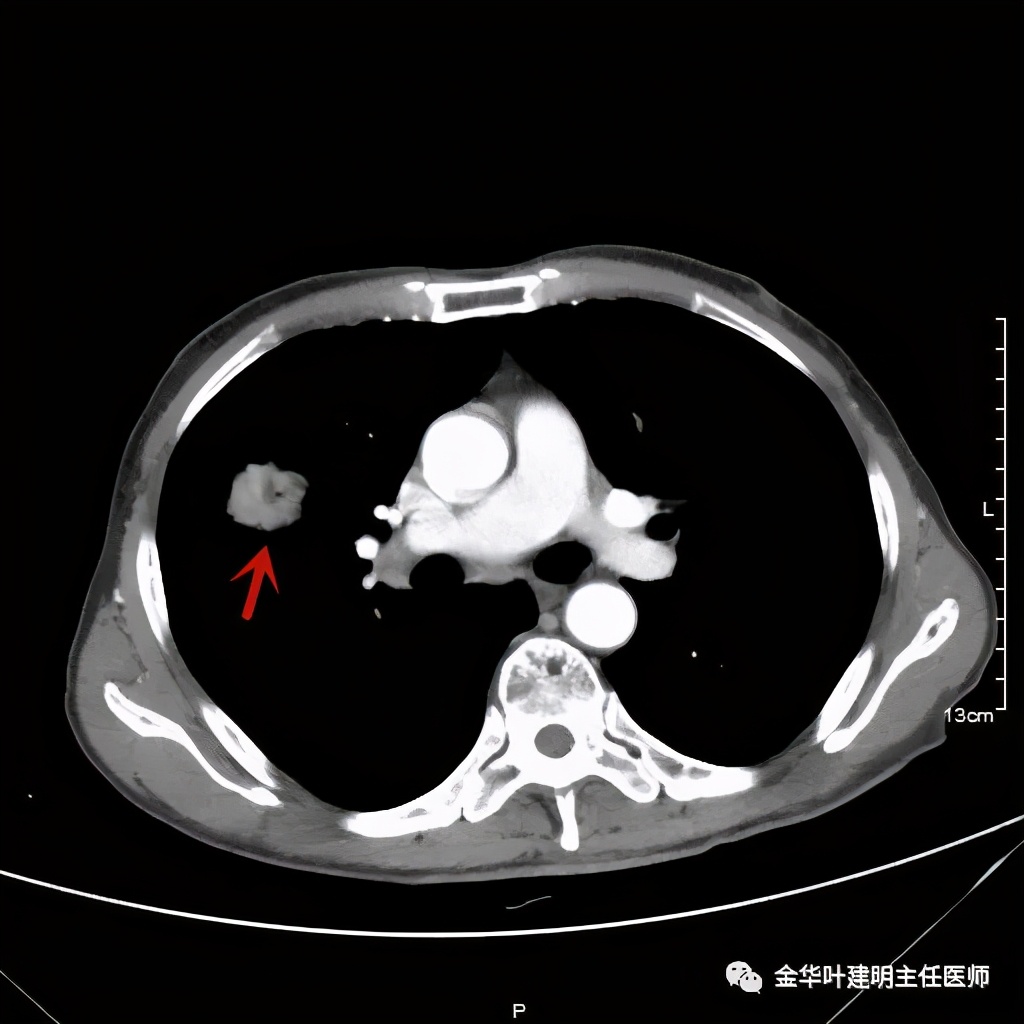

金华的某A,今年73岁,男性。检查发现右上肺占位,肿瘤筛查指标正常,血常规与CRP正常,临床有反复咳嗽、咳痰2年余(考虑慢支的关系,近期也许同时有病灶的影响)。一年前还在外院做过支气管镜,也未见确切异常。我们先来看他这次的胸部CT图像:

上图示病灶

上图示纵隔窗实性